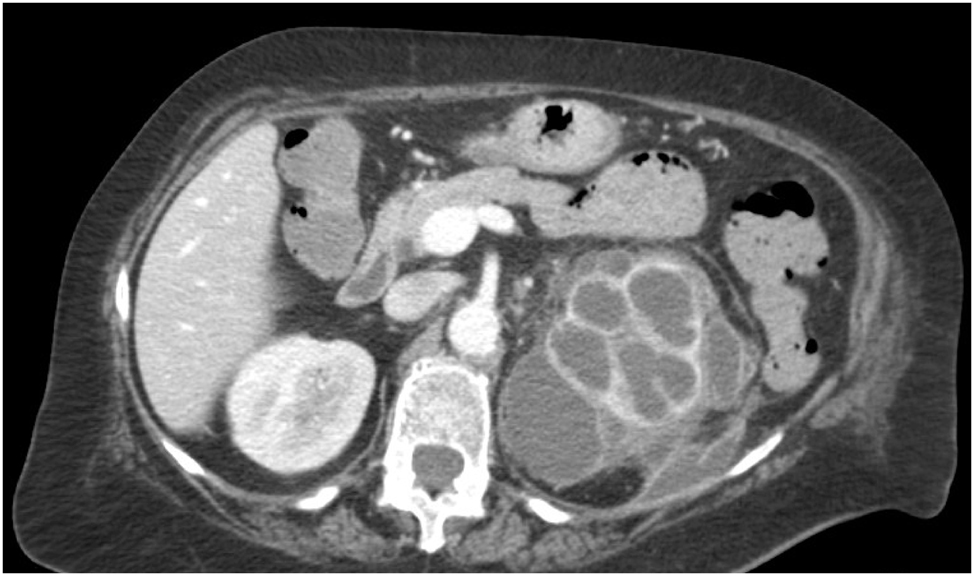

A 73 y-o female patient was referred to “MG Vannini” Hospital in Rome with a complaint of dull persistent left flank pain with intermittent sciatica, general malaise, dysuria, and fever (39 °C): initially, the patient was normotensive but exhibited tachycardia (130/min) and then rapidly, during the first hospitalization hours in Emergy Room, developed respiratory distress and sepsis with drowsiness, hypotension and tachypnea. Blood tests showed leukocytosis (14.3 103/mm3, normal value 4.0–10.0), thrombocytosis (PLT 525 103/mm3, normal value 140–400), increased fibrinogen (>900 mg/dL, normal value 150–400), and C-reactive protein levels (17.0 mg/dL, normal value 0.0–0.5); blood gas analysis in ambient air patient breathing showed pH=7,24, pCO2=50,3 mmHg, pO2=73,7 mmHg, O2 saturation 93 %. This results were compatible with a septic state. Renal function was normal so patient underwent a contrast medium whole body CT scan which showed left pleural empyema (35 mm maximum thickness) associated with ipsilateral lung complete atelectasis and left main bronchus caliber abrupt reduction (Figure 1); the abdominal imaging showed the left kidney with a widespread parenchymal density alteration with reduction of the cortico-medullary boundary, multiple nephrolithiasis even at upper ureter level, with perinephric mostly retro-renal abscess collections (maximum diameter 43 mm), which seem to communicate with the left pleural cavity through a trans-diaphragmatic fistula (Figure 2). The right kidney was normal in shape and excretory function: no left-kidney contrast medium elimination was shown. Chest drain was inserted by Seldinger technique under direct ultrasound guidance obtaining 200 mL of purulent material which resulted in partial respiratory improvement, even if an oxygen supplementation was still required; the perirenal abscess was also drained percutaneously and a broad spectrum intravenous antibiotic was administered (Meropenem 1,000 mg every 8 h). Microbiology specimens from the pleural and perinephric fluids grew Klebsiella pneumoniae which was treated with Piperacillin and Levofloxacin based on culture sensitivity. Starting from the fourth hospitalization day, with empirical antibiotics in progress and therefore before applying the appropriate culture responses-based treatment, patient’s respiratory conditions improved (pH 7.36, pCO2 46.4 mmHg, pO2 91.8 mmHg, O2 saturation 95 %), as did the inflammation (leucocytes=11.2 103/mm3, C-reactive protein levels=13.0 mg/dL); however, a further CT scan showed the pleural empyema and perirenal collection persistence, also reported by the drainage positivity, leading us to proceed with a combined urological-thoracic surgery. With patient’s left side up, at 90° on the operating table to allow simultaneous thoracic approach without changing position, a retroperitoneoscopic left nephrectomy with a wide extra-gerotal dissection was performed; in between the upper pole and left diaphragm a huge pus collection and a trans-diaphragmatic fistula were appreciable, confirming CT findings. The fistulous tract was excised and the diaphragm was closed with 0-0 absorbable interrupted stitches; the retroperitoneoscopy was performed using a valvelss-trocar system (AirSeal®), pre-setting the CO2 pressure between 8 and 10 mmHg thus avoiding increased CO2 absorption and higher end-tidal CO2 and PaCO2, resulting in reduced venous flow and respiratory compliance. These biochemical, vascular and respiratory alterations commonly observed in conventional CO2 insufflation, both with trans-peritoneal and retroperitoneal approach, may be potentially harmful events in one case like ours; moreover the retroperiteoscopy avoided excessive diaphragmatic fibres distension, thus reducing the intrathoracic compression which would have limited the already reduced pulmunary expansion. Even though the working space was small especially in the fistulectomy and diaphragmatic closure phase, the retroperitoneoscopic experience gained over the years by the urology team allowed the operation to be completed without complications, using two straight needle holders and a 2/0 absorbable suture with interrupted stitches. Once the kidney has been removed and complete retroperitoneal cleaning and fistulectomy have been carried out a VAT surgery to decorticate pleural cavity and lung surface was performed by the thoracic surgery equipe. No intraoperative complications were observed; renal histology revealed XGP and renal stones, with multiple renal abscesses. Patient was discharged in 7 post-op day. At time, after one year, patients has not presented infectious pleural/retroperitoneal recurrecences.

Preoperative abdomen contrast-enhanced CT, showing the left kidney with a widespread parenchymal density alteration with reduction of the cortico-medullary boundary and “bear-paw sign”.

The vast majority of complicated pleural effusions and empyemas develop following pulmonary infections, even if chest manifestations of abdominal pathologies are not rare since associations between sub-phrenich collections and exudative pleural effusions have been described; it is known that pulmonary and pleural complications are present in more than 20 % of renal infections and that 1/3 of empyemas due to abdominal pathology [2] is related to pyonephrosis, which may cause peri-renal abscesses from which nephro-pleural or more rarely nephro-bronchial fistulae can develop, causing uroptysis [3]. The perinephric abscess tracks up the superior attachment of Gerota’s fascia where it fuses with the diaphragm: the infected fluid collection makes its way through a trans-diaphragmatic fistula that leads to the ipsilateral pleural cavity, although in some cases congenital malformations of the diaphragm, such as Bochdalek’s foramen or smaller diaphragmatic wall defects [4], facilitate retroperitoneal transit into the chest. The CT scan provides the most correct empyema diagnosis, as it guarantees the mediastinal, chest wall and pleural lesions evaluation showing a picture of unilateral pleural effusion with a consolidation area, sometimes loculated and often with typical “split pleural sign” due to thickened enhancing parietal and visceral layers separated by pleural fluid [5]; the mediastinal lymph-node enlargement and bronchial alterations are also seen, such as extrapleuric tissue thickening and increased attenuation of the extrapelural fat. The most frequently described causes of empyema arising from trans-diaphragmatic fistulas concern complications of percutaneous nephrolithotomy [6], ureteric stenting [7], infected renal cysts [8], but there are also cases due to XGP, a fairly rare complication of chronic pyelonephritis associated with obstructive often lithiasic uropathy, which causes renal parenchyma destruction in such an aggressive manner as to cause fistulas extended to the nearby organs and compartments [9]; for this reason XGP is classified into local extension-linked categories (I – renal parenchyma; II – peri-renal fat; III – para-renal spaces and retroperitoneum) [10], 11]. The XGP is usually unilateral, it affects females twice as often as males with a preference of the right side [12] and may cause also duodenal, cholic, cholecystic, cutaneous fistulas in addition to trans-diaphragmatic ones [13], [14], [15], [16]; the most frequently cultured organisms are Escherichia Coli and Proteus Mirabilis, although it is not uncommon to obtain other culture reports such as K. pneumoniae, Serratia macescens [17], or even sterile urine, and it shows symptoms such as generalized abdominal pain, flank pain sometimes with atypical irradiation depending on the collection extent [18], weight loss, dysuria. The radiological XGP diagnosis can be confusing enough, to have earned the disease the “great imitator” epithet [19], since it presents renal cell tumor (RCC), upper tract urinary cancer (UTUC) or renal tuberculosis radiological signs; CT scan provides typical altough not pathognomonic indications, such as the “bear-paw sign” (FIG.2) [20], and describes extra-renal collections and the fistulous tracts presence. Despite this the diagnosis is histological with a picture of chronic interstitial pyelonephritis and periglomerular fibrosis, rare thyroidisation and tubular atrophy. The management of empyemas due to nephro-pleural fistulas associated with XGP follows similar protocols to those for other causes of empyema [21], requiring nephrectomy and pleural decortication: the retroperitoneoscopic route was chosen to avoid peritoneal contamination, to minimize the diaphragmatic distension which reduces the pulmonary capacity and venous flow thus altering the respiratory compliance already compromised [22], and because it is the most frequently used technique by the Department’s urologists [23], therefore representing a safe surgery. The combined vat-retroperitoneoscopy approach was chosen after careful anaesthesiologic evaluation to avoid patient having to undergo long anaesthesia time, considering the already described respiratory conditions. Moreover keeping the patient in position also useful for VAT (left side up, 90° angle on the operating table), which was performed immediately after the nephrectomy and diaphragmatic fistulectomy, allowed to save time reducing mobilization as much as possible. We evaluated surgical alternatives but the only viable option was the trans-peritoneal laparotomy followed by thoracotomy or vat; in order to avoid respiratory or infectious risks the combined route was preferred.